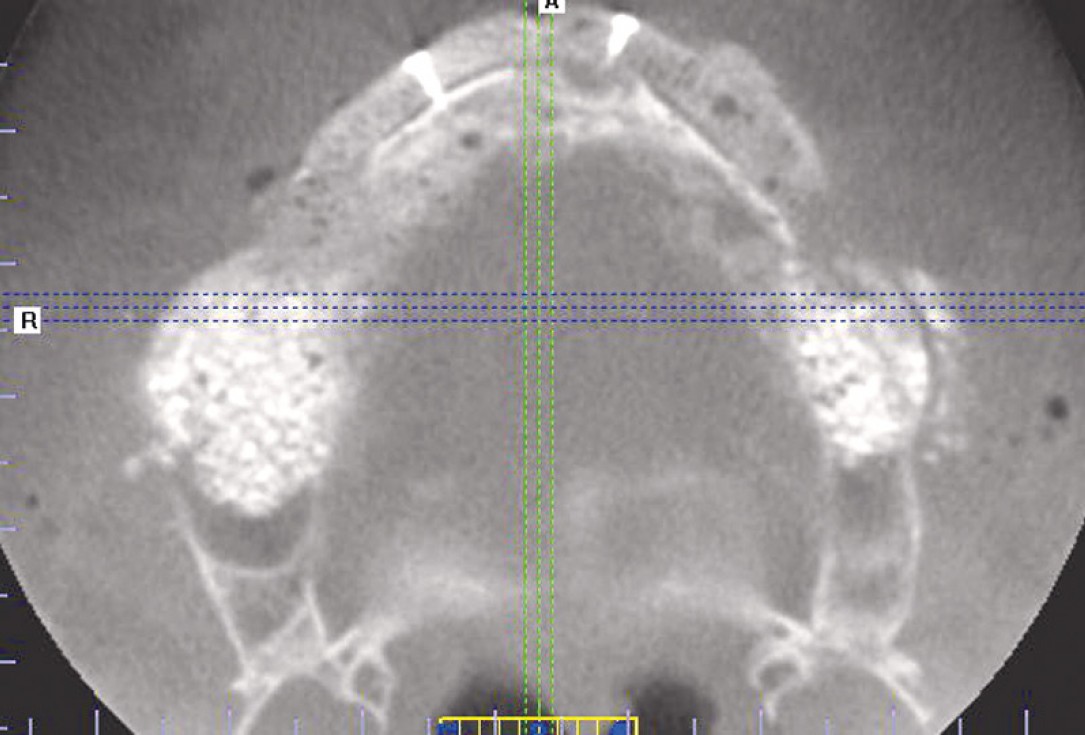

2/23 - Preoperative radiological situation – severely atrophic maxilla

Full arch reconstruction of the maxilla with maxgraft® bonebuilder - Dr. M. Erbshäuser